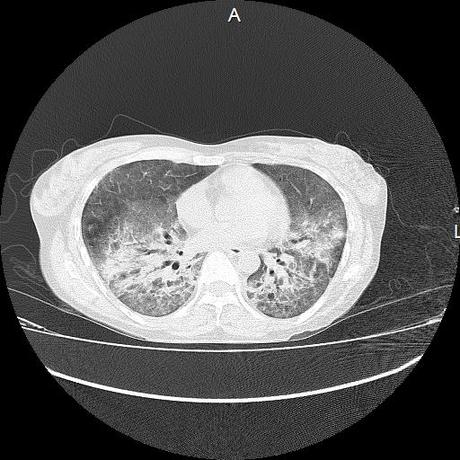

El parénquima pulmonar con areas parcheadas difusas en vidrio despulido combinadas con otras areas hipodensas de baja atenuación debidas a atrapamiento aéreo y engrosamiento intersticial y zonas de fibrosis de predominio en lóbulos medios e inferiores de ambos pulmones.

- LOS HALLAZGOS PUEDEN ESTAR EN RELACIÓN A NEUMOPATIA INTERSTICIAL PROBABLE ETIOLOGIA HIPERSENSITIVA VS AUTOINMUNE/BACTERIANA/FUNGICA.